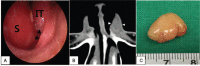

Rationale: Neurilemmoma is a benign tumor derived from the Schwann cells of the nerve sheath. The highest incidence of neurilemmoma occurs in the head and neck region; however, the nose and paranasal sinuses are rarely involved. Less than 4% of these tumors involve the nasal cavity and paranasal sinuses. To date, only six cases of nasal vestibule neurilemmoma have been reported.

Patient concerns: Two patients (a 32-year-old man and a 42-year-old woman) visited our clinic with complaint of a lump in the left nasal vestibule.

Diagnosis: Histopathological examination and immunohistochemical staining confirmed a neurilemmoma.

Interventions: The mass was completely removed via an intranasal approach.

Outcomes and lessons: Neurilemmoma is easy to overlook because it occurs rarely in the nasal vestibule, but neurilemmoma needs to be considered as a differential diagnosis.